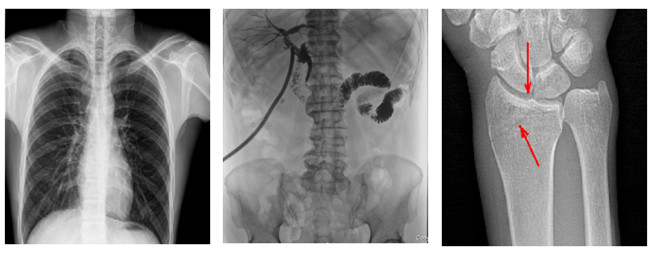

普利德多功能懸吊動態DR,搭載100μm高品質動態平板探測器,不僅滿足常規的數字化X線全身攝影需求,同時還擁有數字攝影、數字透視、數字造影、全景拼接等多種功能,極大地拓展了X線檢查在臨床應用范圍,為醫院臨床應用帶來更多實用價值。基于百微平板的高清成像,圖像清晰度與分辨率更高,可滿足不同檢查部位對細節成像的高品質要求,在胸腹部、脊柱等復雜骨骼和軟組織的攝片上應用,更便于觀察隱匿性病灶,精準識別疑難病癥。

不同于靜態DR拍攝隱匿性病灶時,由于組織重疊病灶難辨,耗費時間更長且易漏診、誤診,普利德多功能懸吊動態DR可通過動態實時連續成像,對于重疊部位病灶或者易被遮擋的病灶進行多角度動態觀察,毫秒級時間內實現動靜態轉換點片,快速、精準完成攝片。比如隱匿性肋骨骨折,可在透視下觀察患者的呼、吸過程,避開重疊影像,快速點片,保證檢查部位的病癥不被遺漏,實現精準診斷。